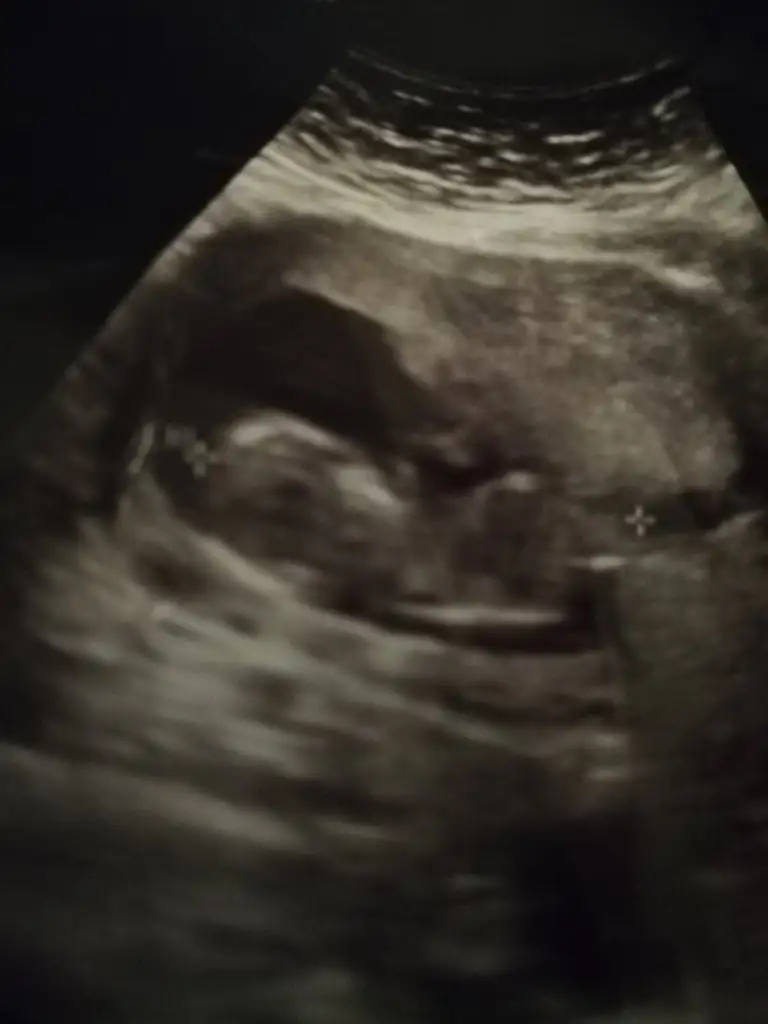

Kız gibi kesede neydi tahminKızlar daha önceydi keseyi atmıştımbirde böyle 12+5ten bir fotomuz var sizce tahminini nedir? 13+4 olduk öğrenemedim çok merak ediyorum